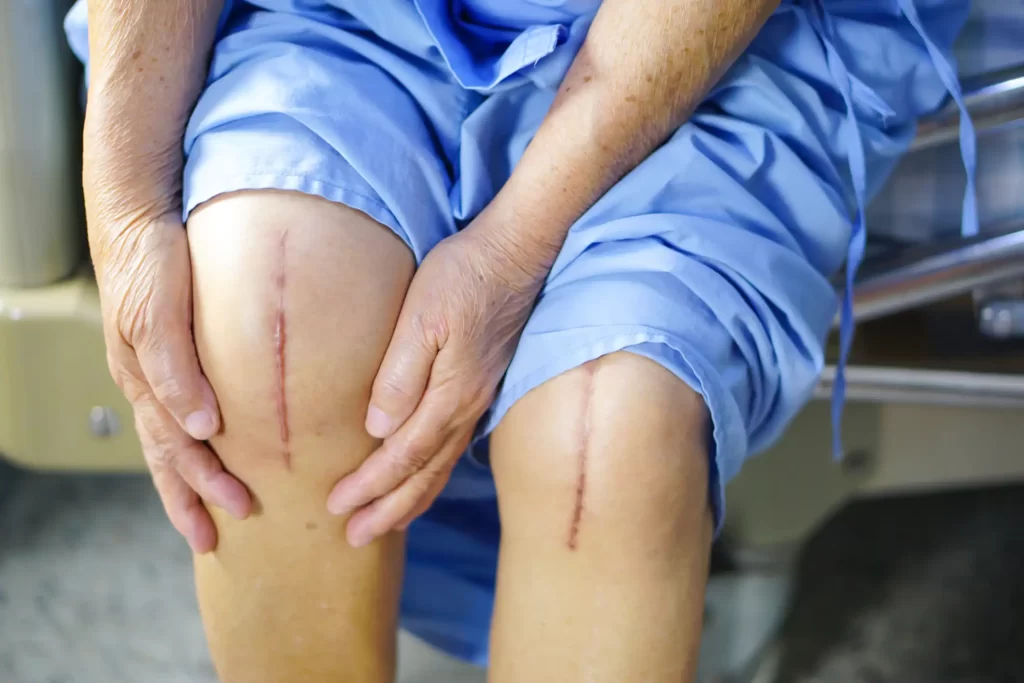

آیا عمل تعویض مفصل زانو خطرناک است؟

سؤالی که اکثر بیماران قبل از تصمیم به جراحی  می‌پرسند این است که آیا عمل تعویض مفصل زانو خطرناک است؟ در پاسخ باید گفت که  اگر تمام اطلاعات مربوط به جراحی و به ویژه خطرات و عوارض آن را به طور کامل درک نکرده‌اید، نباید تحت عمل جراحی تعویض کامل زانو قرار بگیرید. به همین دلیل در این بخش به بررسی خطرات جراحی تعویض مفصل زانو و عوارض احتمالی آن می‌پردازیم. اگر قصد انجام عمل تعویض مفصل زانو را دارید، توصیه می‌کنیم این بخش را مطالعه کنید.

تعویض مفصل زانو